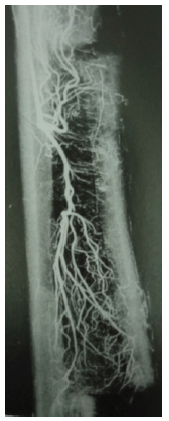

A small 5 incisions were made at the anterolateral part of the tibia. The distance between two incisions are 2cm. Through each 5 incisions a 5mm osteotome is used to do the osteotomy so that we can osteotomize the incised tibia in a colinear fashion. In the proximal incision we should cut the bone 2cm transversely. After that below each incision’s osteotomy 1.8mm 5 olive wires were introduced to connect with lateral plate via slotted bars. The tibial section has been moved approx. 1 mm/day for 3 weeks. The clinical status improved within a few weeks. Cure of trophic ulcers and no more pain. Arteriogram on the 2nd months improved circulatory result.3–7

The diabetic foot ulcer under the great toe and little toe are seen in most of the cases. Pre surgery color duplex confirmed the extrusive occlusion of anterior tibia, posterior tibia, and anteria dorsalis pedis. After surgery with 5 days of interval we started distraction of the osteotomised bone with the plate. Tibial section has been moved approximately 1 mm per day for 3 weeks. The clinical condition improved in 3 weeks and cure of diabetic foot ulcer were seen.

3. Distraction angiogenesis.